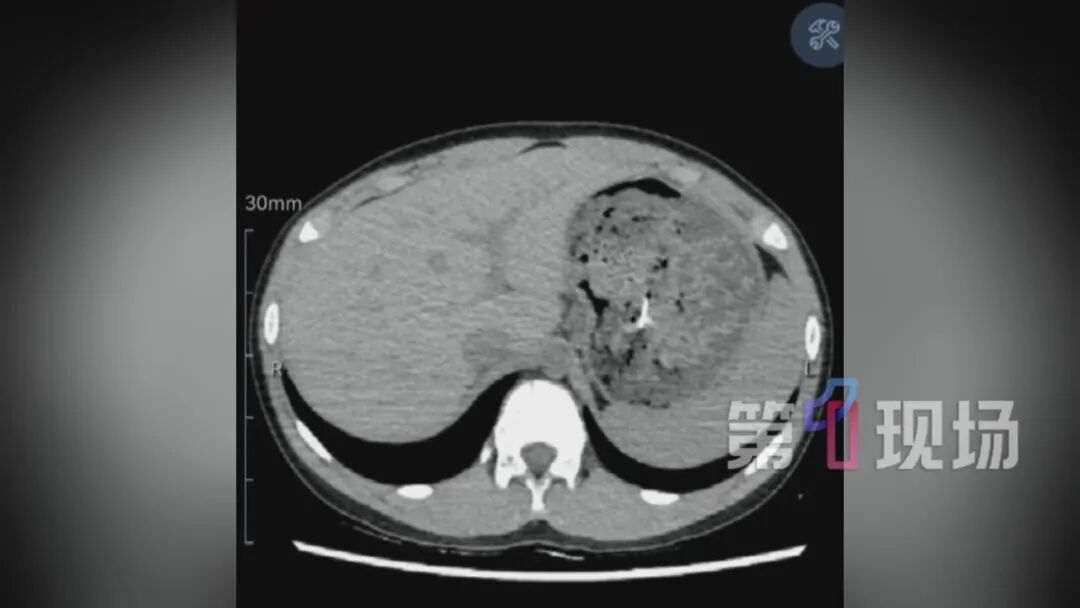

在当地医院CT检查显示,大头针已经进到胃腔里了。但孩子刚吃完牛肉面,胃里全是食物残渣,想要取出这个大头针没那么容易。医生评估后,建议立即转诊,家长便立马带着孩子去了南方医科大学深圳医院。

3.5厘米的大头针混在胃里的食物残渣中,要把它找出来,难度堪比大海捞针;

经过30分钟的专注搜寻,医生终于锁定了大头针的针尖位置——它正静静“躺”在食物残渣中,银色的针尖格外显眼。

手术中取出的大头针大约3.5厘米,银白色的针已经被胃酸腐蚀变黑,一旦耽误的时间过长,后果不堪设想。